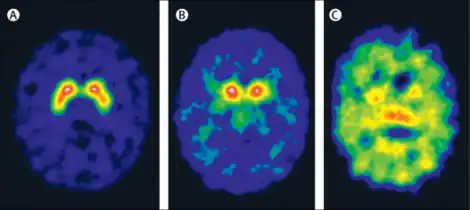

Diagnosis of SLC6A3-negative DTDS is established in a proband via molecular genetic testing, looking for biallelic (i.e. homozygous or compound heterozygous) pathogenic SLC6A3 variants. DTDS-positive patients are further identified by matching their genetic testing results with known characteristic clinical, laboratory, and imaging findings.[5]